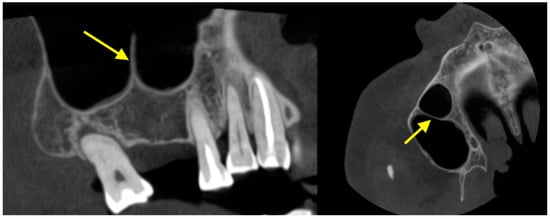

3.1. Membrane Thickening Associated with Periapical Lesions